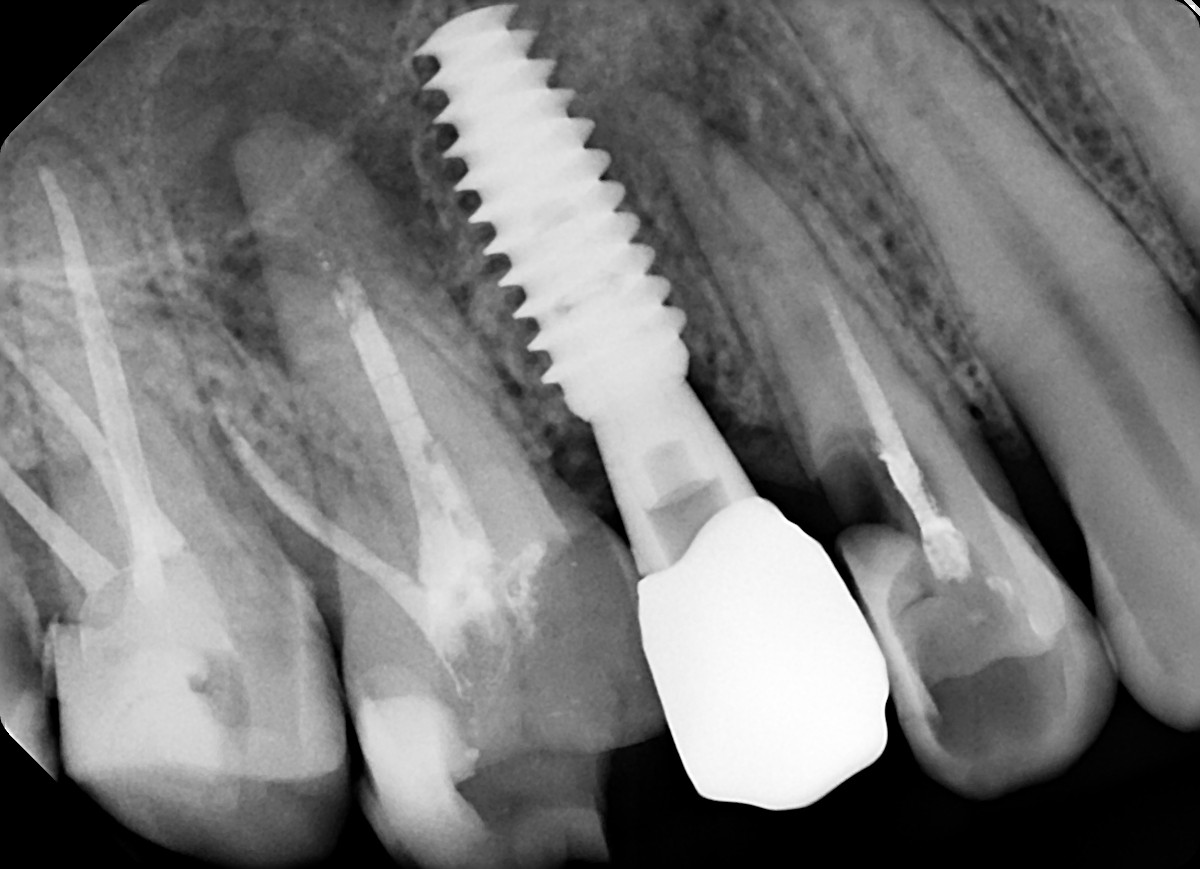

1. Evaluate the root canal treatment of tooth # 2.5?

2. What option cannot be selected for root canal treatment of tooth # 2.6?